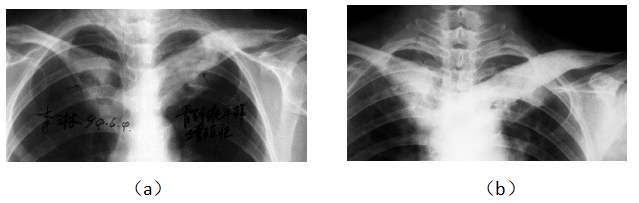

病例10 女,55岁,双侧锁骨骨纤维异样增殖症5年,疼痛严重,经治疗6个月痊愈.

Case 1, female, 55 years old, bone fiber dysplasia for 3 years, severe pain, cured after eating for 6 months. Before eating, the clavicles, sternum and the first rib on both sides were thickened and deformed, with uneven density (a). After eating, the density of clavicle, sternum and the first rib on both sides were more uniform than before (b).